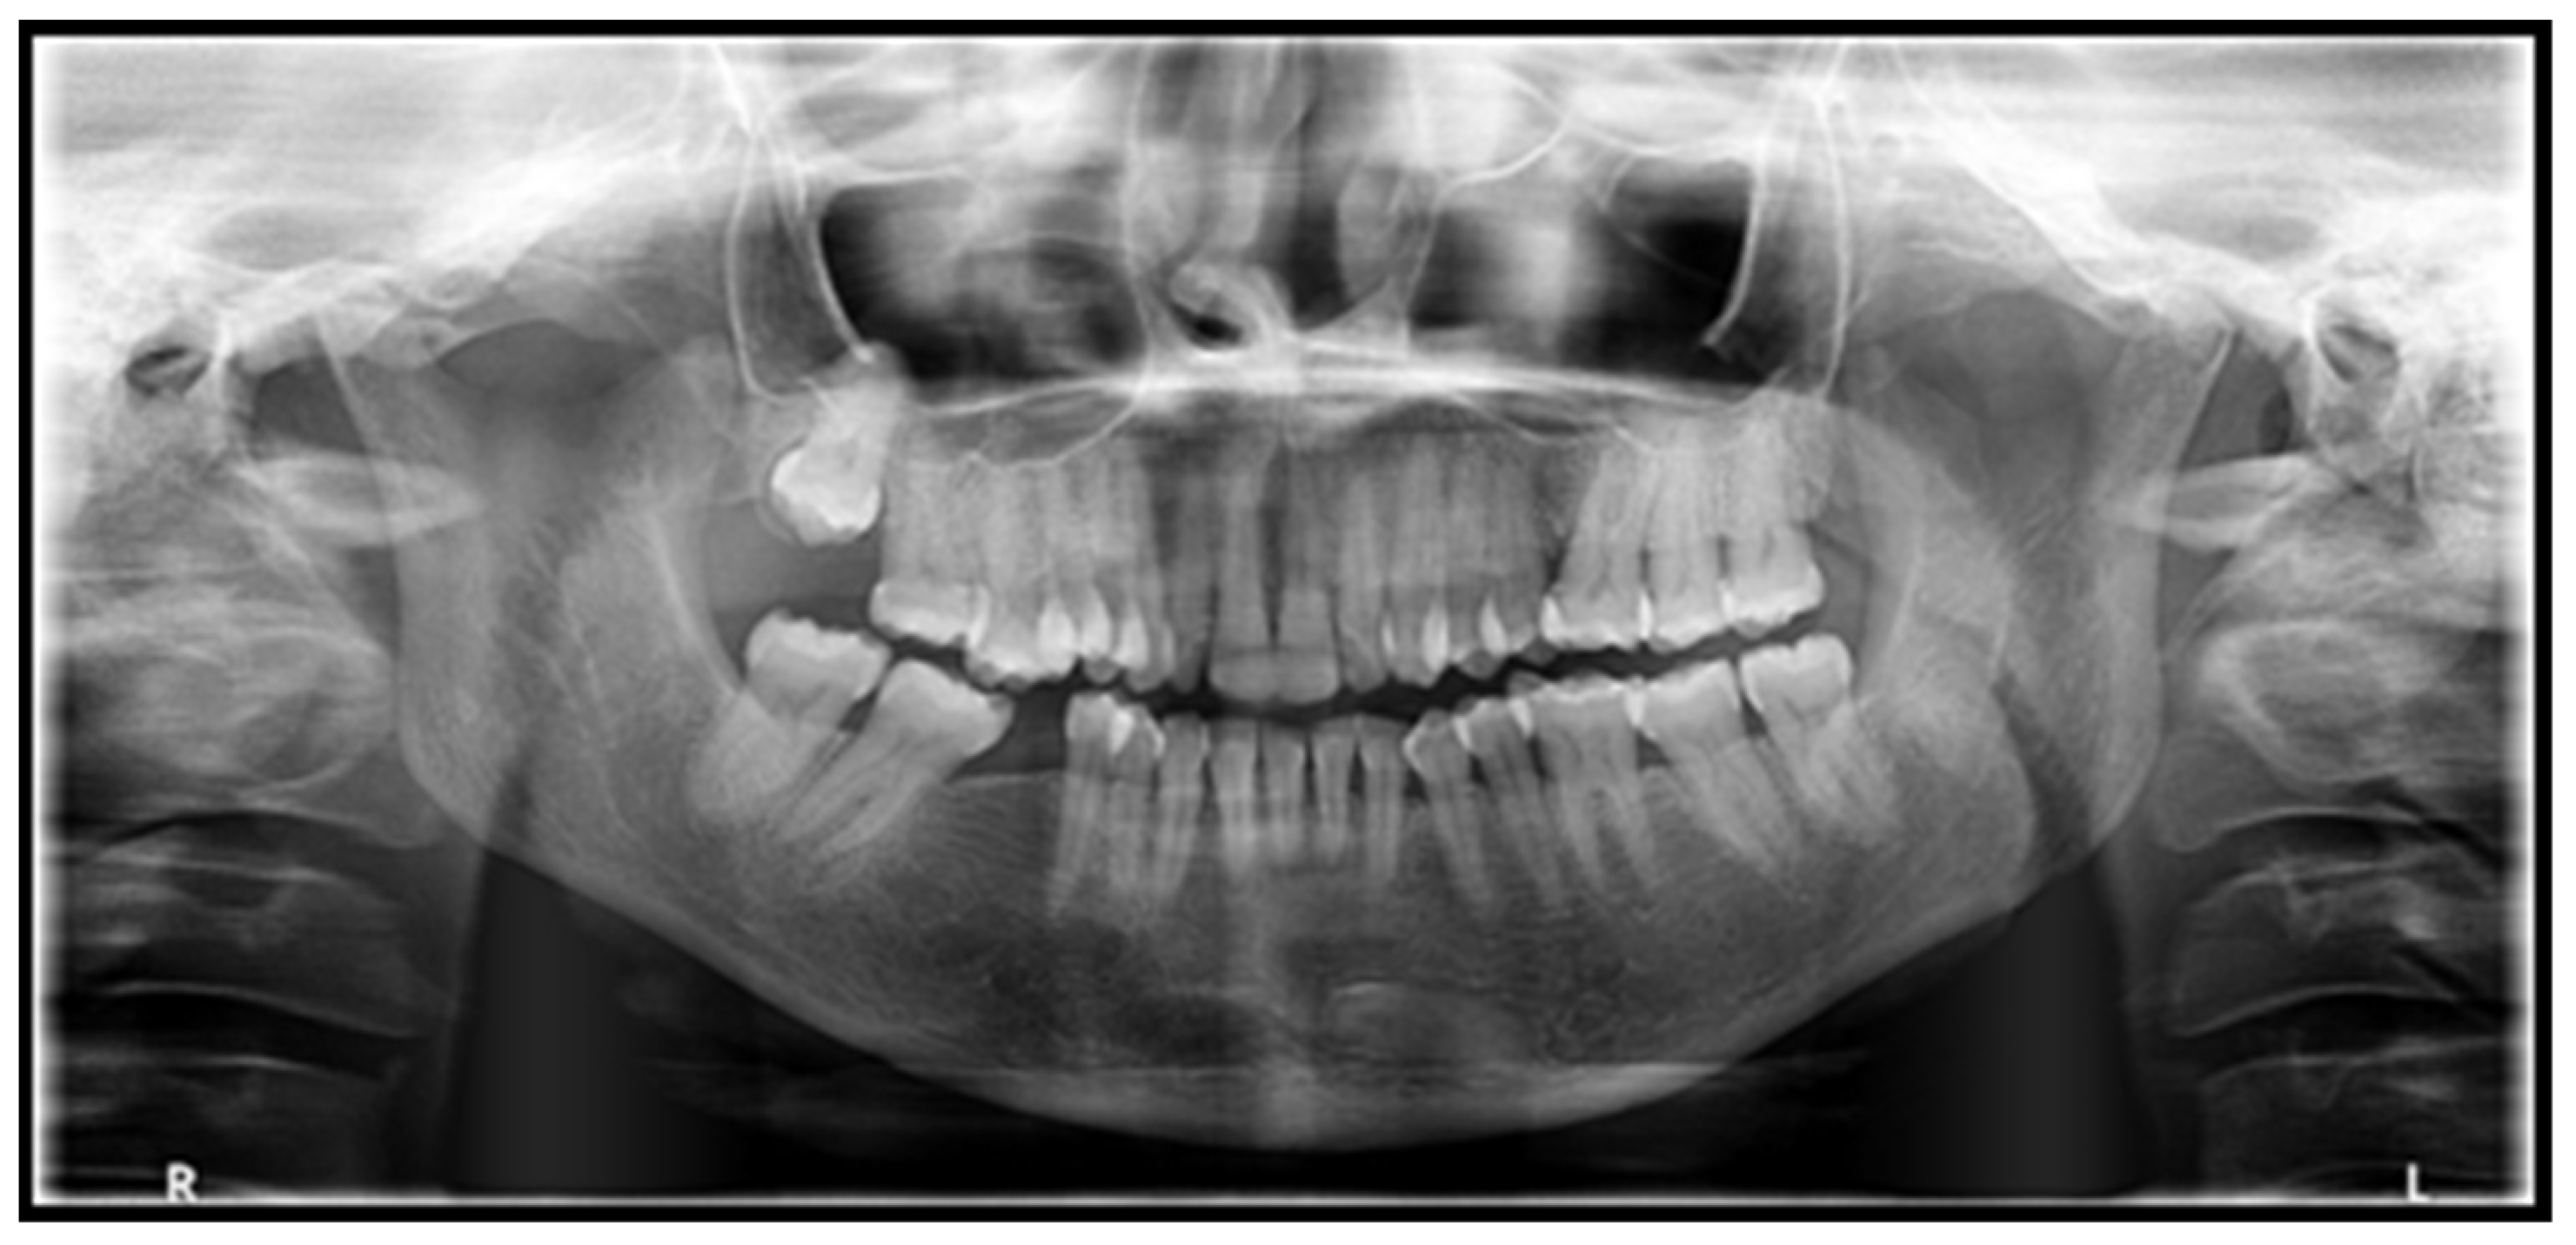

Orthopantomogram (OPG) showed generalized PDL space widening, especially pronounced in the right and left mandibular and left maxillary posterior teeth, with mild interdental bone loss seen. Mild flattening of the left condyle was also noticed (Figure 3).

Periodontal ligament space widening and mandibular erosions are the distinctive radiographic manifestations of SSc [8]. Periodontal ligament space widening is the most frequently occurring radiographic presentation, and SSc should be given a place in the differential diagnosis, where the radiographic features demonstrate widened PDL space with intact lamina dura (particularly in non-mobile posterior teeth with widened PDL space in more than one segment) [36].

Another radiographic manifestation reported in these patients is the presence of bilateral, sharply defined, relatively uniform mandibular erosions at the insertion sites of masticatory muscles (angles, coronoid process, condyles, or digastric region) [36]. The blunting of mandibular angles results in a characteristic “tail of the whale” radiographic appearance [9].

The radiographic findings seen in our patient included a widened PDL space (more pronounced in posterior teeth) with intact lamina dura and a slight flattening of the left condylar head.

Figure 3. OPG reveals generalized PDL space widening. Mild flattening of the left condyle was also appreciated.